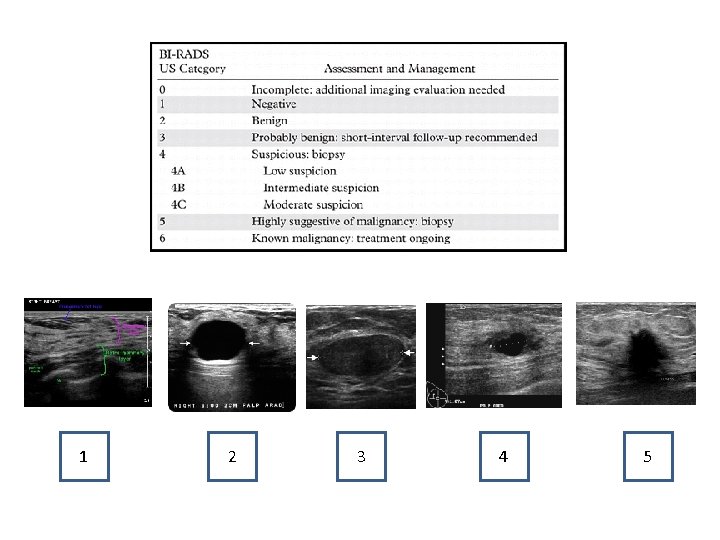

1 2 3 4 5

A 24 you woman undergoes a breast ultrasound for a self-palpated left breast mass. You order a breast ultrasound which is demonstrated below. What Bi-Rad classification is this lesion? 1. Bi-Rads 0 2. Bi-Rads 1 3. Bi-Rads 2 4. Bi-Rads 4

A 63 you woman undergoes a breast ultrasound for a self-palpated left breast mass. Her diagnostic breast ultrasound is demonstrated below. What Bi-Rad classification is this lesion? 1. Bi-Rads 0 2. Bi-Rads 1 3. Bi-Rads 2 4. Bi-Rads 5

Which Bi-Rads classification recommends 6 month short term follow up imaging? 1. Bi-Rads 0 2. Bi-Rads 2 3. Bi-Rads 3 4. Bi-Rads 4